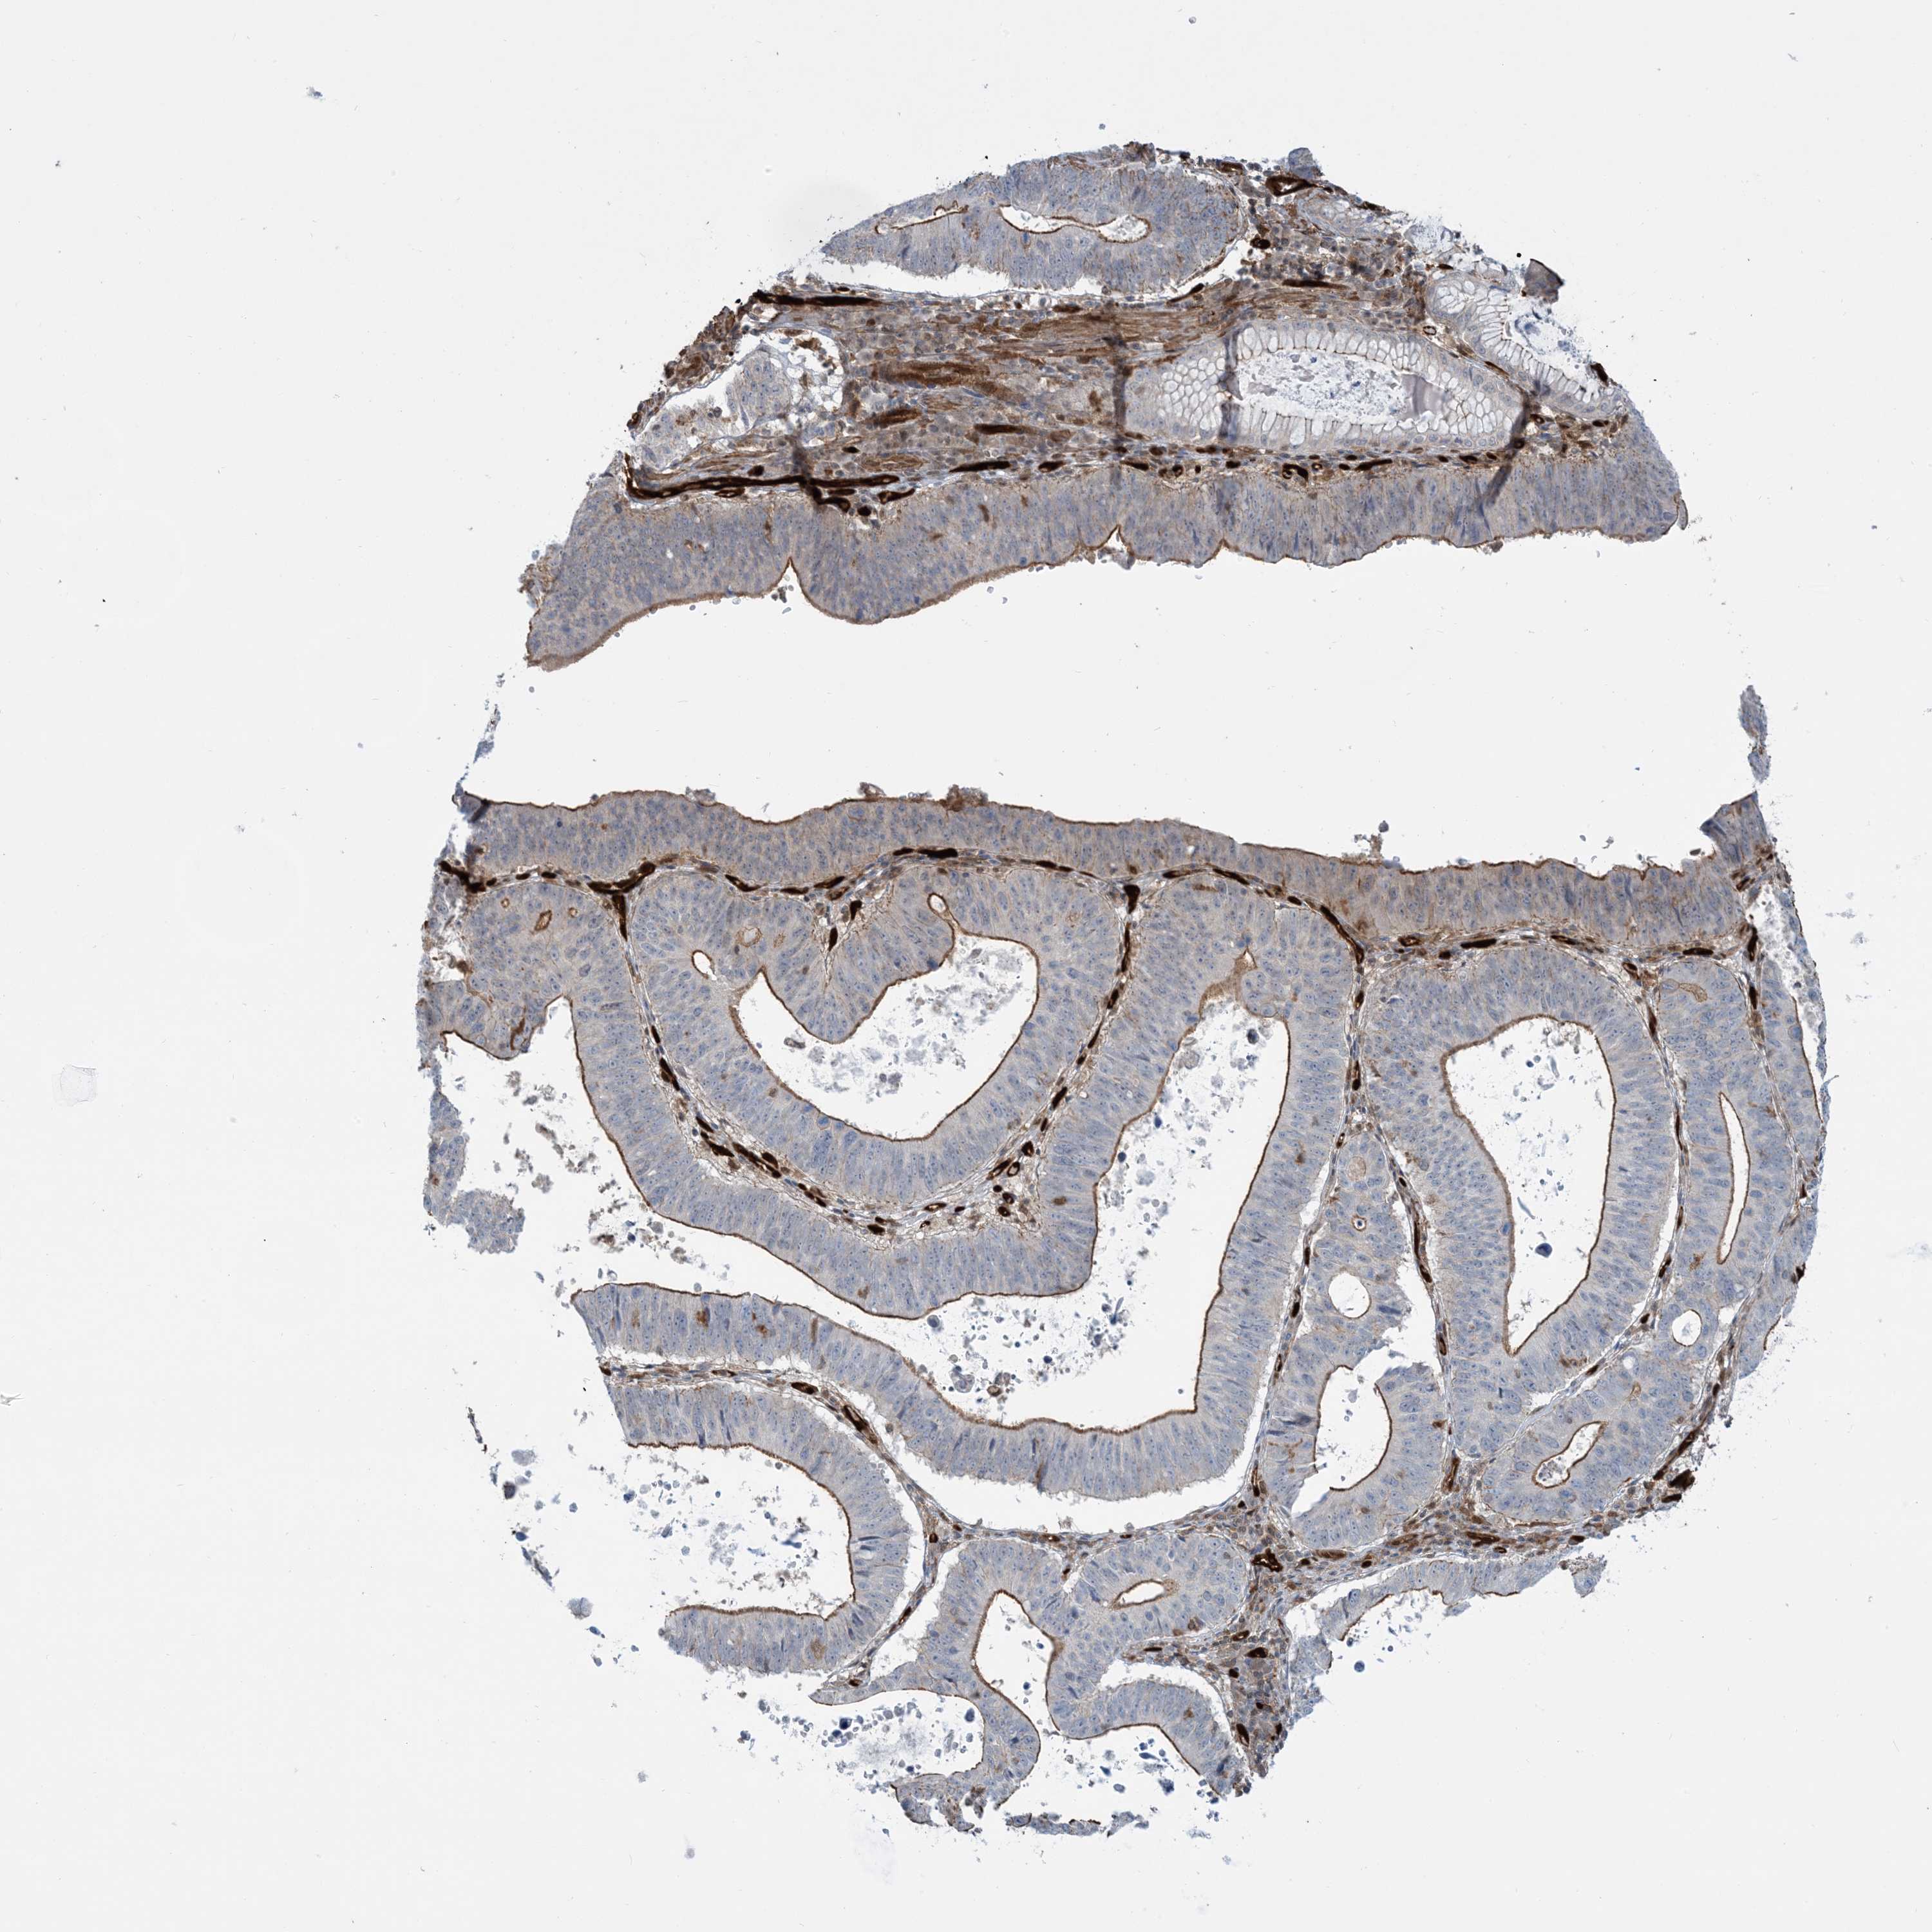

STOMACH CANCER - Protein expressioni

A mouse-over function shows sample information and annotation data. Click on an image to view it in a full screen mode. Samples can be filtered based on level of antibody staining by selecting one or several of the following categories: high, medium, low and not detected. The assay and annotation is described here.

Note that samples used for immunohistochemistry by the Human Protein Atlas do not correspond to samples in the TCGA dataset.

Antibody stainingi

Antibody staining in the annotated cell types in the current human tissue is reported as not detected, low, medium, or high, based on conventional immunohistochemistry profiling in selected tissues. This score is based on the combination of the staining intensity and fraction of stained cells.

Each image is clickable and will lead to virtual microscopy that enables deeper exploration of all samples and also displays staining intensity scores, fraction scores and subcellular localization as well as patient and tissue information for each sample.

Antibody HPA030989

Antibody HPA030990

Staining

High

Medium

Low

Not detected

Intensity

Strong

Moderate

Weak

Negative

Quantity

>75%

75%-25%

<25%

None

Location

Nuclear

Cytoplasmic/membranous

Cytoplasmic/membranous,nuclear

Adenocarcinoma, NOS